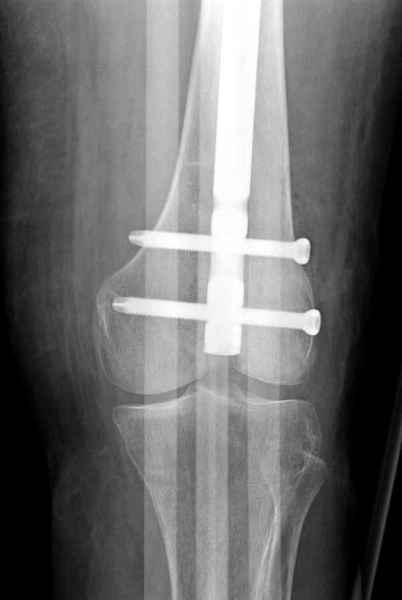

С минимальным рассверливанием и ретроградным методом провели остеосинтез бедра 12 мм гвоздем. (17-20)

Кровопотеря во время операции меньше 100 мл.